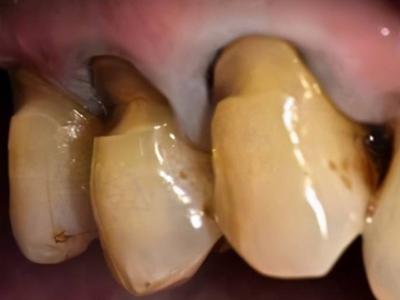

酸蚀症牙齿缺损严重有黄斑图

酸蚀症严重时可导致牙齿发生大块缺损,上门牙侧面有较大空洞,形似虫蛀,缺损处颜色明显发黄,呈黄褐色至深褐色,需积极进行牙齿修复治疗。

酸蚀症牙齿根部有黄斑及缺损图

酸蚀症患者的牙齿根部会出现黄斑,呈黄色至茶褐色,牙骨质缺损,形成坑洼,牙根变薄并暴露在外,黄斑下方还有白垩状斑片。其发生与口腔长期接触酸性物质有关。

酸蚀症牙齿缺损变薄有黄斑图

酸蚀症患者的牙齿会发生缺损,表面骨质被腐蚀,牙齿变薄,缺损处有黄斑形成,呈土黄色至黄褐色。此时牙齿易被折断,需进行牙齿修复治疗。